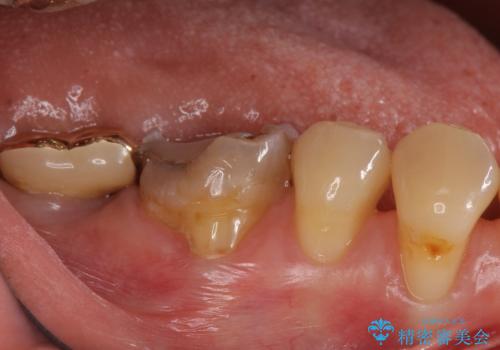

- 昔つめた材料が欠けたこと、歯の捻転を主訴に来院されました。

矯正治療の希望はなかったため、被せ物で歯の形を修正することになりました。

不適合だった詰め物の裏側に大きな虫歯がありました。

セラミックインレーやアンレーでは強度に不安が残るため、クラウンでの修復処置としました。

クラウンでは歯のがたつきを修正することもできます。

虫歯の除去と歯の捻転の両方を解決することができました。